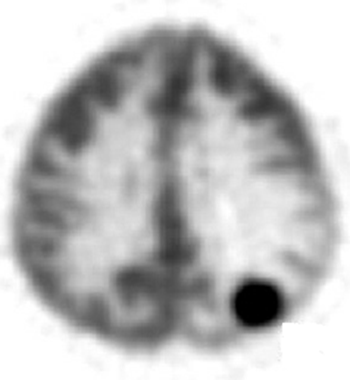

what is the organ of this image

brain

what is view of this image

transaxial (transverse) slice

what are the results of the scan

brain metastases